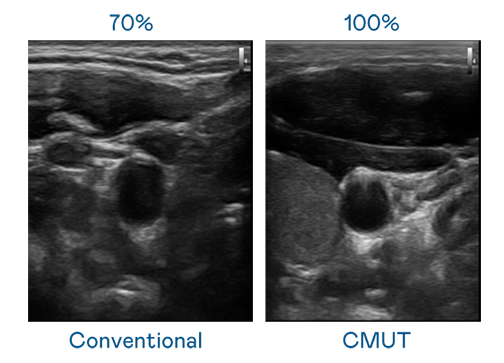

CMUT 技术是一种用电容式微机电元件来产生超音波讯号的技术。与传统 PZT 压电式技术相比,CMUT 频宽增加 30%,更宽频的超音波讯号让影像解析度大幅提升,是实现高影像品质医疗超音波扫描、促进精准医疗发展的关键技术。

超音波影像的解析度高低,首先取决于探头能发出的讯号频宽。BJL平台 CMUT 可提供高清晰的超音波讯号,提供高频宽、高灵敏度、影像纹理细节更高的超音波影像,协助医护人员缩短影像判读时间及利用精准的医疗影像进行诊断。